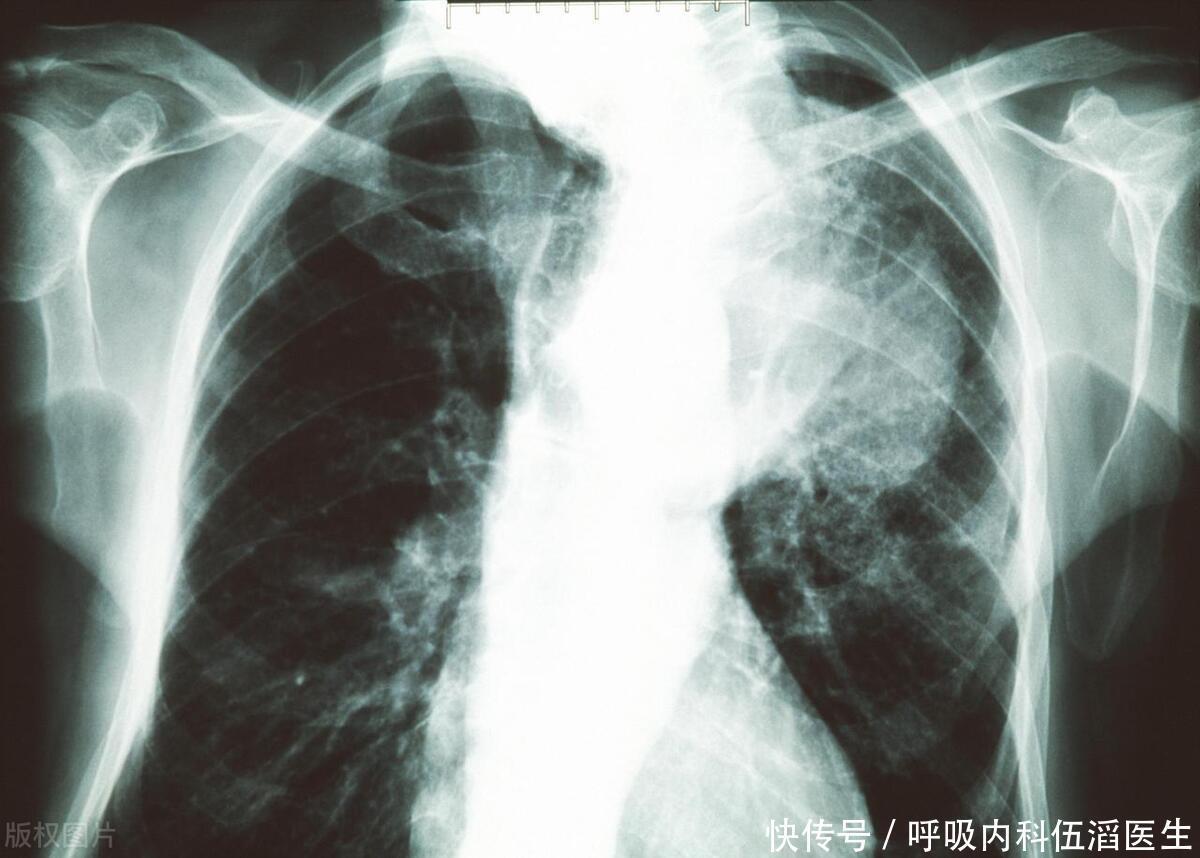

肺癌,这一曾经被视为“富人病”的恶性肿瘤,如今已逐渐渗透到普通百姓家中。据统计,我国每年有高达82万人被确诊为肺癌,这一数字令人触目惊心。我们还应积极预防肝癌的发生,通过改善生活习惯、定期体检等方式,降低肝癌的发病率和死亡率,守护我们的肝脏健康。除了众所周知的吸烟、空气污染等外在因素,家中隐藏的三大“肺癌致癌物”同样不容忽视。本文将深入剖析这些隐藏在家中的致癌物,并给出相应的清理建议,帮助大家打造一个健康的生活环境。